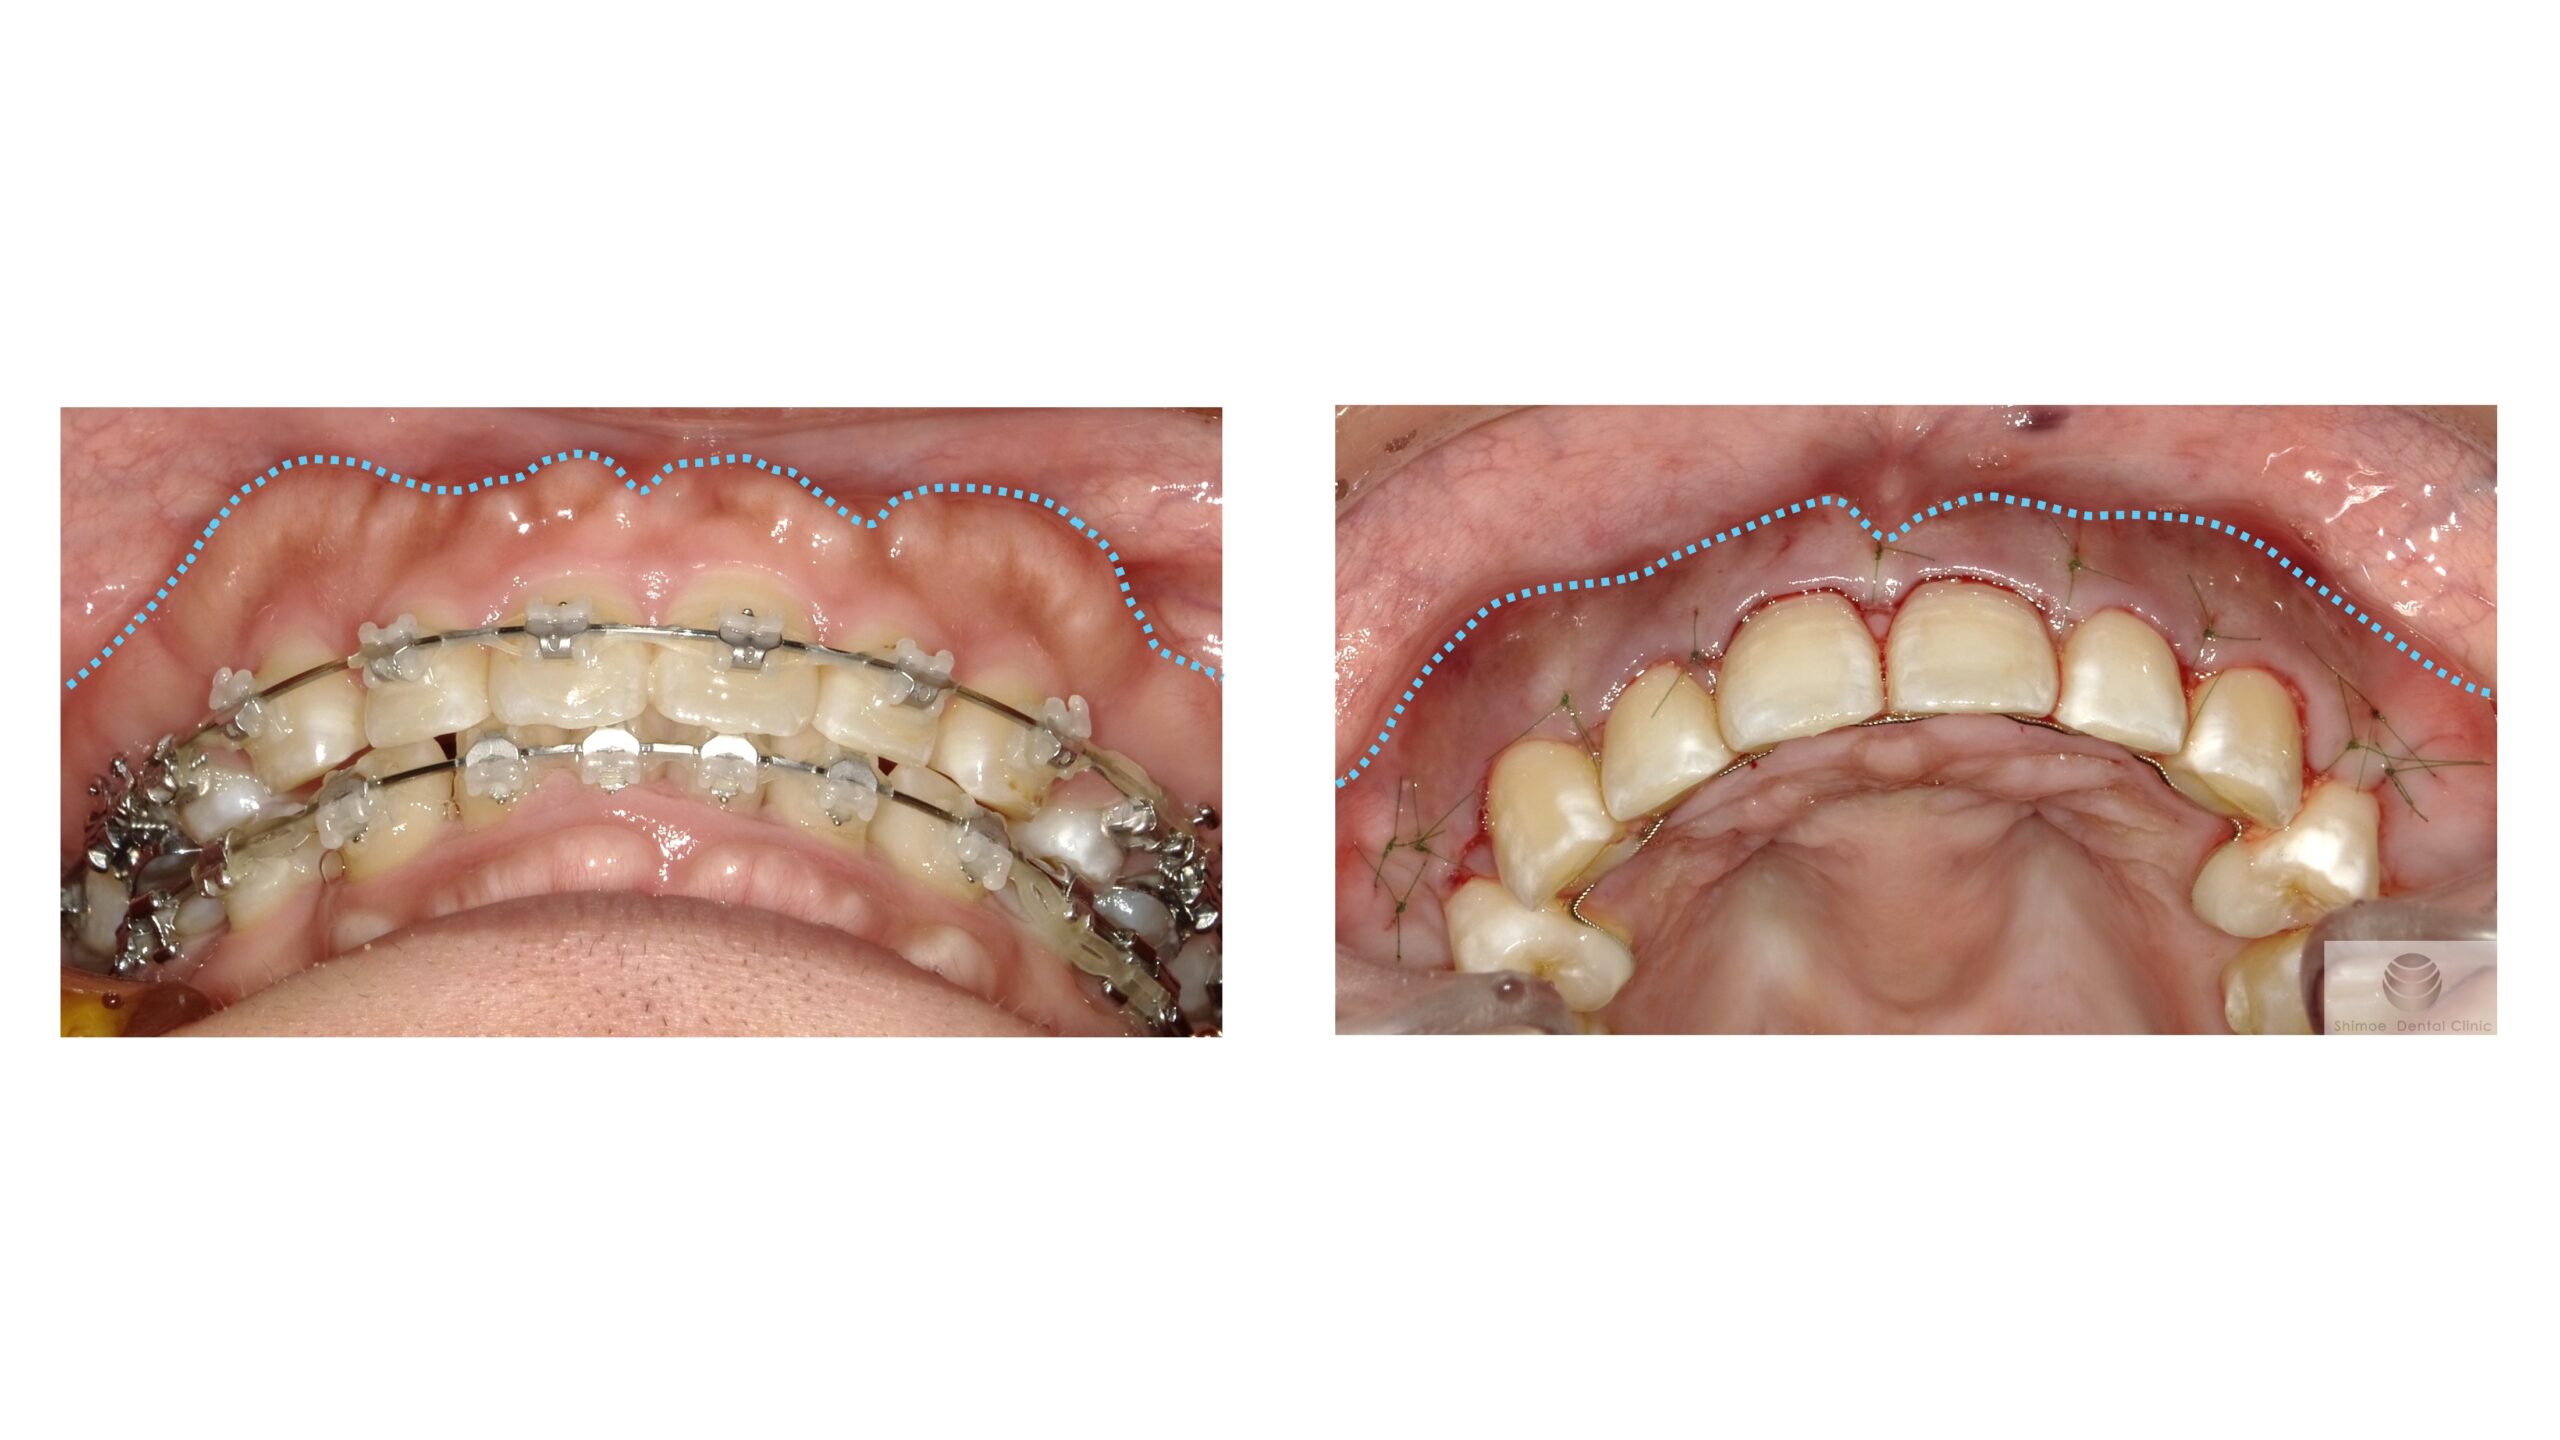

手術前後比較

下からのアングルでの術前後比較写真

もとの骨隆起のラインを水色点線で記しています。

厚み、幅ともに大きく切除しています。